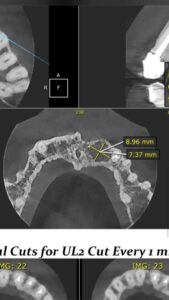

تمكّن فريق طب الأسنان بمستشفى جهينة المركزي، تحت إشراف الدكتور باهر نعيم، مدير عام طب الأسنان، والدكتور محمد مرتضى، مدير المستشفى، من إجراء عملية جراحية نوعية. استهدفت العملية إزالة كيس مرضي كان ينمو تحت القاطع الأول والثاني بالفك العلوي لفتاة تبلغ من العمر 23 عاماً.

واستغرقت الجراحة الدقيقة نحو ساعة ونصف فقط تحت التخدير الموضعي. وقد تكللت بالنجاح التام، حيث أزال الأطباء الكيس المرضي كاملاً، في سابقة هي الأولى التي يُسجلها مستشفى جهينة المركزي في هذا النوع من الجراحات المتخصصة.